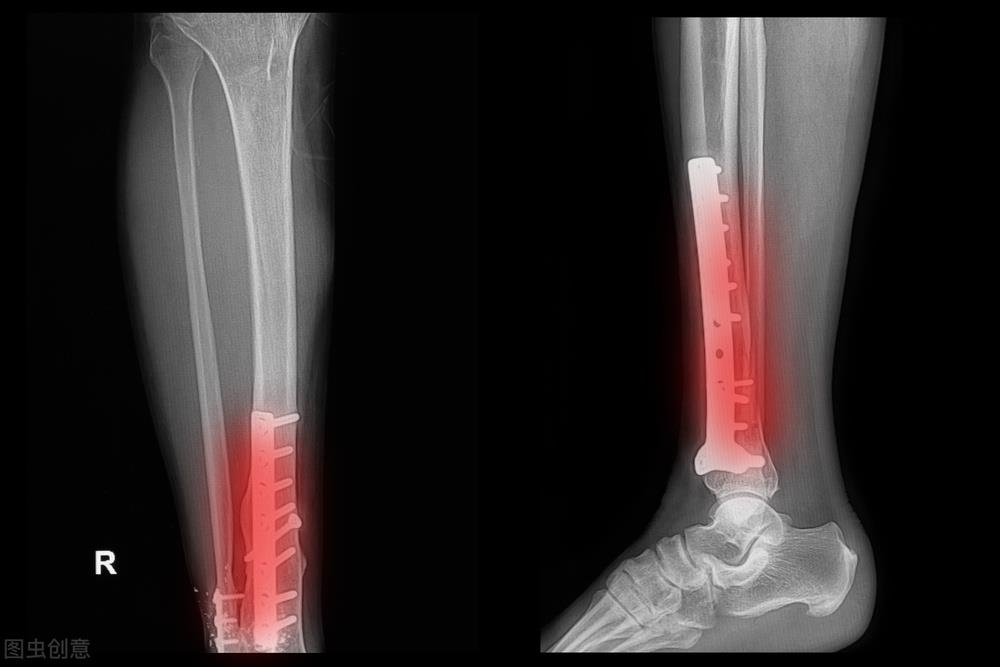

另外,保障的不同往往会产生最后结果的巨大差异!2002年我就亲眼见证了这么一个案例:那年,一名上海籍的纯体力劳动者因为自己的不慎操作在外轮上摔断了左腿胫骨,事后他不仅得到了近三万元的赔偿,而且获得了半年的带薪休假——工资全额,奖金按照同期同工种奖金的一半发放;无独有偶,第二年一名外包劳务工发生了相同的事故,最后的处理结果是给了一万块补偿,然后直接送回原籍!我想任何人都可以在这个案例中感受良多!

胫骨